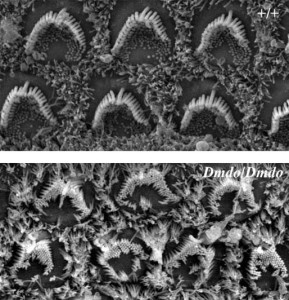

I ricercatori hanno scoperto che è possibile analizzare il ruolo della mutazione nei topi. Come hanno affermato i ricercatori, sembra le cellule ciliate sensorie nel topo mutante siano disturbate dal gene miR-96. Mentre i topi portatori delle due copie del gene mutante presentavano cellule ciliate deformi dalla nascita e cellule soggette a una degenerazione già nei primi stadi di vita, i ricercatori hanno scoperto che gli effetti erano meno gravi nei topi che presentavano una sola copia del gene mutante. Tuttavia, hanno osservato gli scienziati, gli effetti si aggravavano con l’aumentare dell’età.